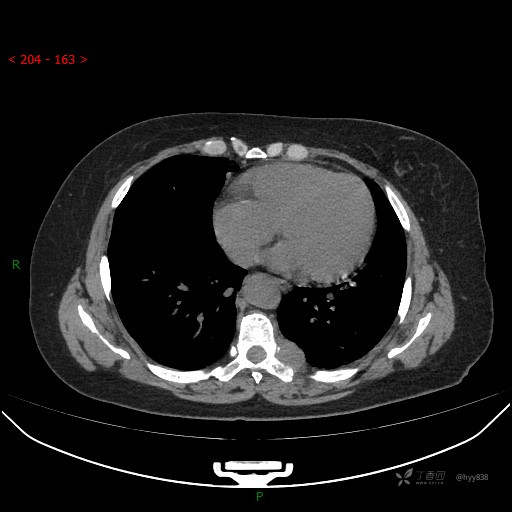

增强